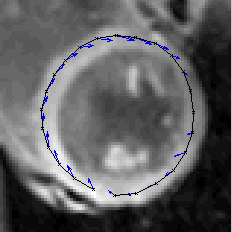

Cardiovascular MRI

Cardiovascular MRI is one of our key research fields. In close collaboration with the clinical research group, new MRI methods are investigated aiming for the assessment of the